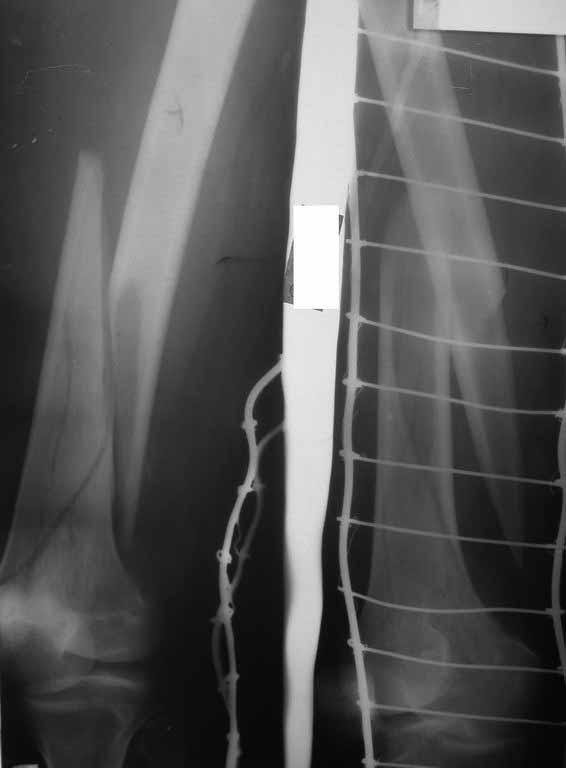

Уважаемые коллеги! 5.08.11 синтез бедренной кости пластиной LCP для дистального бедра.

Прошу совета. П-ка, 59 лет, автодорожная травма, перелом винтообразный н/3 левой бедренной кости. Планировалась закрытая репозиция и малоинвазивный доступ. по ходу операции пришлось немного открыть зону перелома для репозиции. Под контролем ЭОП вроде на столе смещение небольшое было и по оси терпимо. Сделали рентген контроль и получили вот картину. Еще обломилась головка кортикального винта. Синтез то стабильный. Только смещение не только не устранили, но кажется еще чуть больше стало (не могу) первичный снимок сделать). Склонен к ресинтезу и исправлению смещения из расширенного доступа. Как лучше выполнить репозицию? Какие можно использовать приемы репозиции? Спасибо.

конечно реостеосинтез, у Вас нижнии шуруп в линии перелома.

тип 32А1 - межфрагментарная компрессия стягивающим винтом + нейтрализующая пластина(если говорить о накостном остеосинтезе, кроме того пластинку бы подлинее этак на см 5). Ну а лучше - гвоздь с блокированием - закрыто, стабильно, с нагрузкой в послеоперационном периоде.

Коллега,для адекватной оценки перелома необходимо предоставлять предоперационные и послеоперационные снимки в двух проекциях. Насколько возможно судить по маленькой картинке прямой проекции, на первый взгляд тут простой винтообразный перелом 32-А1. В таком случае самый стабильный вариант накостного остеосинтеза - это стягивающий винт перепендикулярно линии перелома и нейтрализирующая пластина. Особых показаний к малоинвазивному мостовидному остеосинтезу нет, т.к. при нем ниже стабильность фиксации, и все микродвижения сконтрентрируются в сравнительно небольшой зоне перелома, что приведет к большим смещающим силам. Однако, если присмотрется, на снимке видно что линия перелома продолжается до начала медиального мыщелка, поэтому скорее всего это клиновидным перелом со спиральным клином 32-В1. В таких случаях возможно выполнение мостовидного синтеза, однако в данном случае дистальная часть клина не смещена относительно дистального конца бедренной кости, таким образом, мне кажется, биомеханически ситуация представляет собой среднее между А1 и чистым В1. Смещающие усилия концентрируются в проксимальной части перелома, тогда как в дистальной несмещенной части они минимальны, в т.ч. из-за интактной надкостницы. Поэтому в данном конкретном случае, при невозможности выполнения интрамедуллярного блокирующего остеосинтеза, я бы выполнил остеосинтез с двумя стягивающими винтами (с рассверливанием ближнего кортикала сверлом большего диаметра) и нейтрализирующего остеосинтеза пластиной. Причем пластина могла бы быть даже обычная.

На представленных снимках, репозиции нет, есть вальгус. Полагаю фиксация не стабильна. Перелом может и срастется, но это будет долго и без нагрузки. Если бы была использована обычная пластина, можно было бы попробовать малоинвазивно подтянуть дистальный отломок и зафиксиривовать парой винтов. Однако примененные блокирующие винты не позволят этого сделать. Как вариант, возможно открытся снизу удалить винты, сделать небольшой доступ в зоне перелома (или попробовать закрыто) ввести 1-2 винта для фиксации клина, и перепровести блокирующие дистальные винты. В любом случае, стабильность при любом из этих вариантов будет заведомо ниже чем при стягивающих винтах + нейтрализирующей пластине. Удачи.